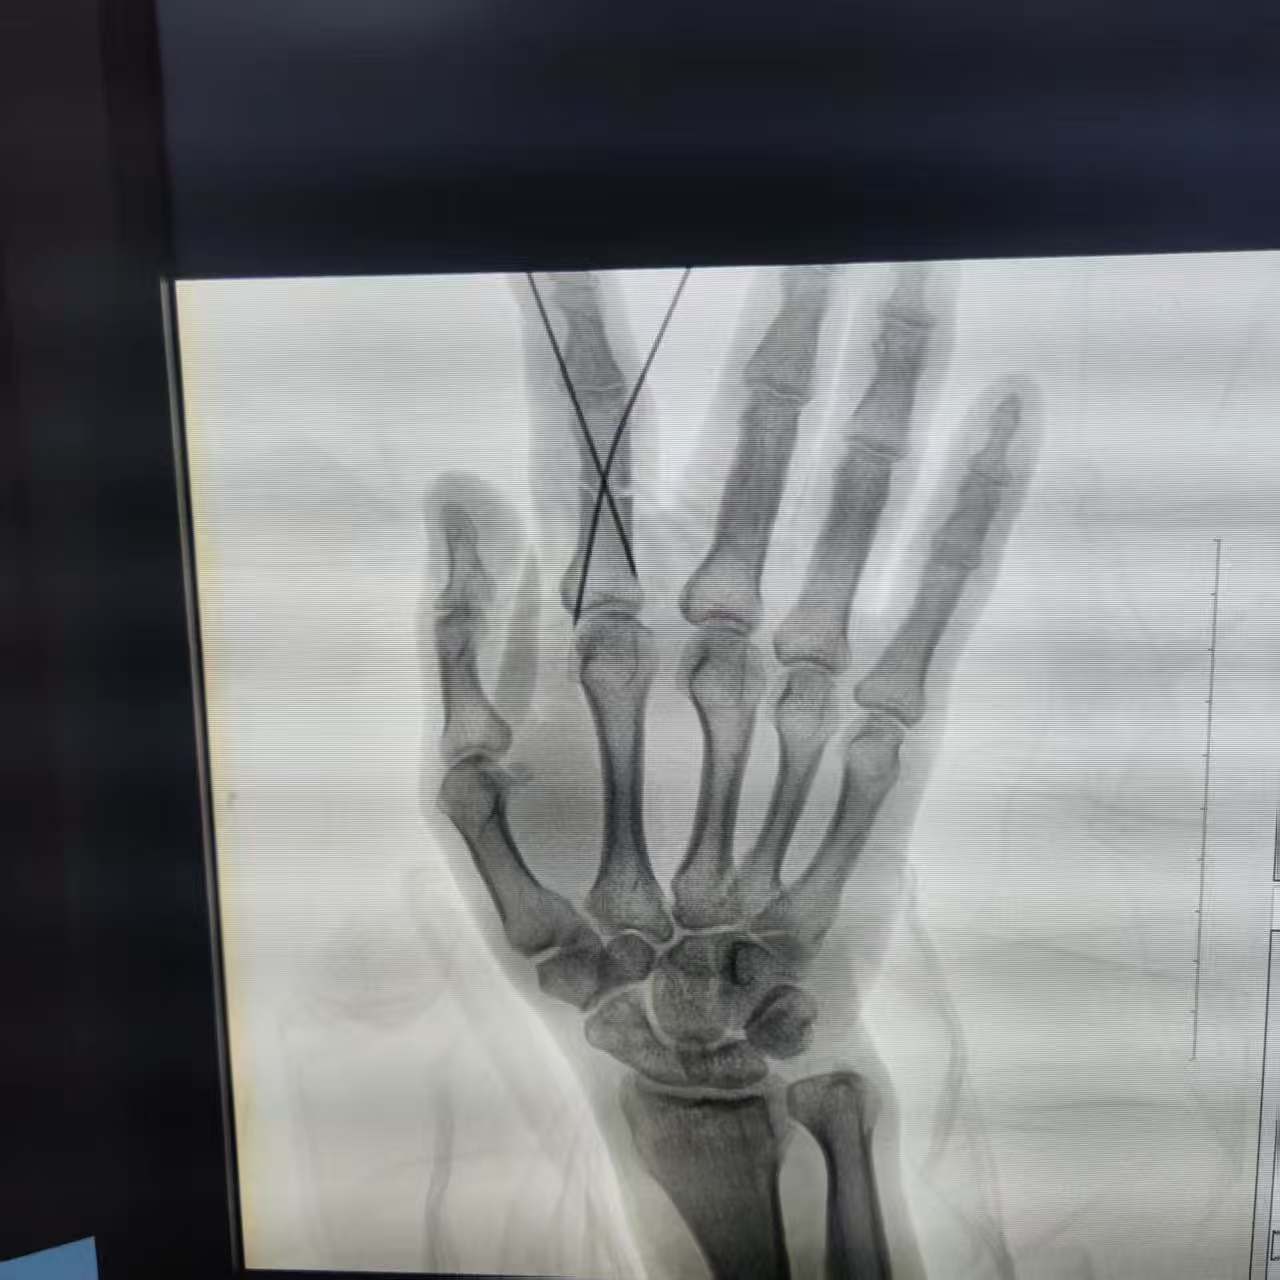

此时,医院创伤骨科副主任李金鑫医生正好值班,他迅速赶到现场。经过详细的询问和X线片拍摄,李医生对黄先生的伤情有了全面的了解。

为了尽快帮助黄先生恢复健康,李医生带领团队进行了深入的病情讨论,并决定采用“刘氏正骨+精准化手术”的治疗手法。在高清C臂的透视下,他们认真清创,精准地放置了两枚钛针,以稳定地固定骨折断端。同时,结合刘三屋刘氏正骨手法,整个手术过程仅用了27分钟,且全程无痛。